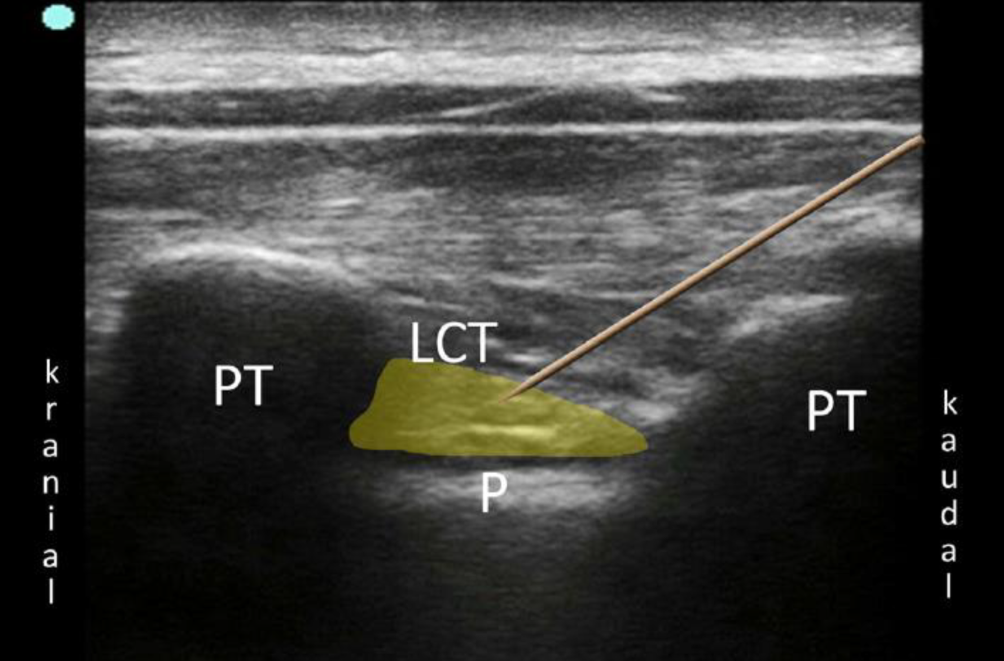

Bei der PVB wird ein Lokalanästhetikumdepot in den Paravertebralraum eingebracht. Hierzu werden Patient*innen in Seitenlage, Bauchlage oder eine sitzende Position gebracht. Sonographisch wird lateral des Processus spinosus zwischen Rippe und Querfortsatz die interne Interkostalmembran dargestellt. Dies kann in transversaler und sagittaler Schallausrichtung erfolgen, mit anschließender Punktion „in plane“ zum Schallkopf, entweder von lateral oder kranial kommend (Abb. 1). Bei korrekter Lage der Spitze der Punktionskanüle im Paravertebralraum tritt häufig ein Widerstandsverlust auf, und bei der Injektion weitet sich der Paravertebralraum mit konsekutiver Verschiebung der Pleura nach ventral (Abb. 2). Für einen Single shot oder das initiale Aufspritzen des Katheters können 15–20 ml 0,2- bis 0,5 %ige Ropivacainlösung verwendet werden; beim katheterbasierten Verfahren sollte die Laufrate maximal 5–6 ml/h betragen [31].

Abb. 1

Anlage einer Paravertebralblockade in sagittaler (a) und transversaler (b) Schallausrichtung. (Aus Steinfeldt et al. [31])

Abb. 2

Sonographische Darstellung einer sagittalen thorakalen Paravertebralblockade. PT Processus transversus, P Pleura, LCT Lig. costotransversarium superius. Lokalanästhetikum gelb dargestellt. (Aus Steinfeldt et al. [31])